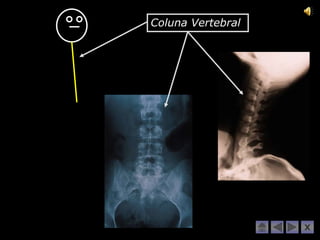

Coluna Vertebral

Ilíaco Muito bem!!! Carpo e Metacarpo Coluna Vertebral Falanges da mão Tíbia e Perónio Úmero e Clavícula Tarso e Metatarso Rótula Rádio e Cúbito Crânio Falanges do pé Fémur Externo e Costelas